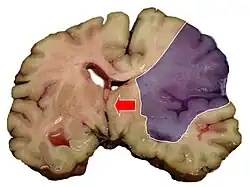

Midline shift

Midline shift is a shift of the brain past its center line.[1] The sign may be evident on neuroimaging such as CT scanning.[1] The sign is considered ominous because it is commonly associated with a distortion of the brain stem that can cause serious dysfunction evidenced by abnormal posturing and failure of the pupils to constrict in response to light.[1] Midline shift is often associated with high intracranial pressure (ICP), which can be deadly.[1] In fact, midline shift is a measure of ICP; presence of the former is an indication of the latter.[2] Presence of midline shift is an indication for neurosurgeons to take measures to monitor and control ICP.[1] Immediate surgery may be indicated when there is a midline shift of over 5 mm.[3][4] The sign can be caused by conditions including traumatic brain injury,[1] stroke, hematoma, or birth deformity that leads to a raised intracranial pressure.

Three main structures are commonly investigated when measuring midline shift. The most important of these is the septum pellucidum, which is a thin and linear layer of tissue located between the right and left ventricles.[7] It is easily found on CT or MRI images due to its unique hypodensity.[7] The other two important structures of the midline include the third ventricle and the pineal gland, which are both centrally located and caudal to the septum pellucidum.[6][7] Identifying the location of these structures on a damaged brain compared to an unaffected brain is another way of categorizing the severity of the midline shift. The terms mild, moderate, and severe are associated with the extent of increasing damage.

Midline shift measurements and imaging has multiple applications. The severity of brain damage is determined by the magnitude of the change in symmetry. Another use is secondary screening to determine deviations in brain trauma at different times after a traumatic injury as well as initial shifts immediately after.[3] The severity of shift is directly proportional to the likeliness of surgery having to be performed. The degree of MLS can also be used to diagnose the pathology that caused it. The MLS measurement can be used to successfully distinguish between a variety of intracranial conditions including acute subdural hematoma,[5][7] malignant middle cerebral artery infarction,[3] epidural hematoma, subarachnoid hemorrhage, chronic subdural hematoma, infarction, intraventrical hemorrhage, a combination of these symptoms, or the absence of pertinent damage altogether.[7]